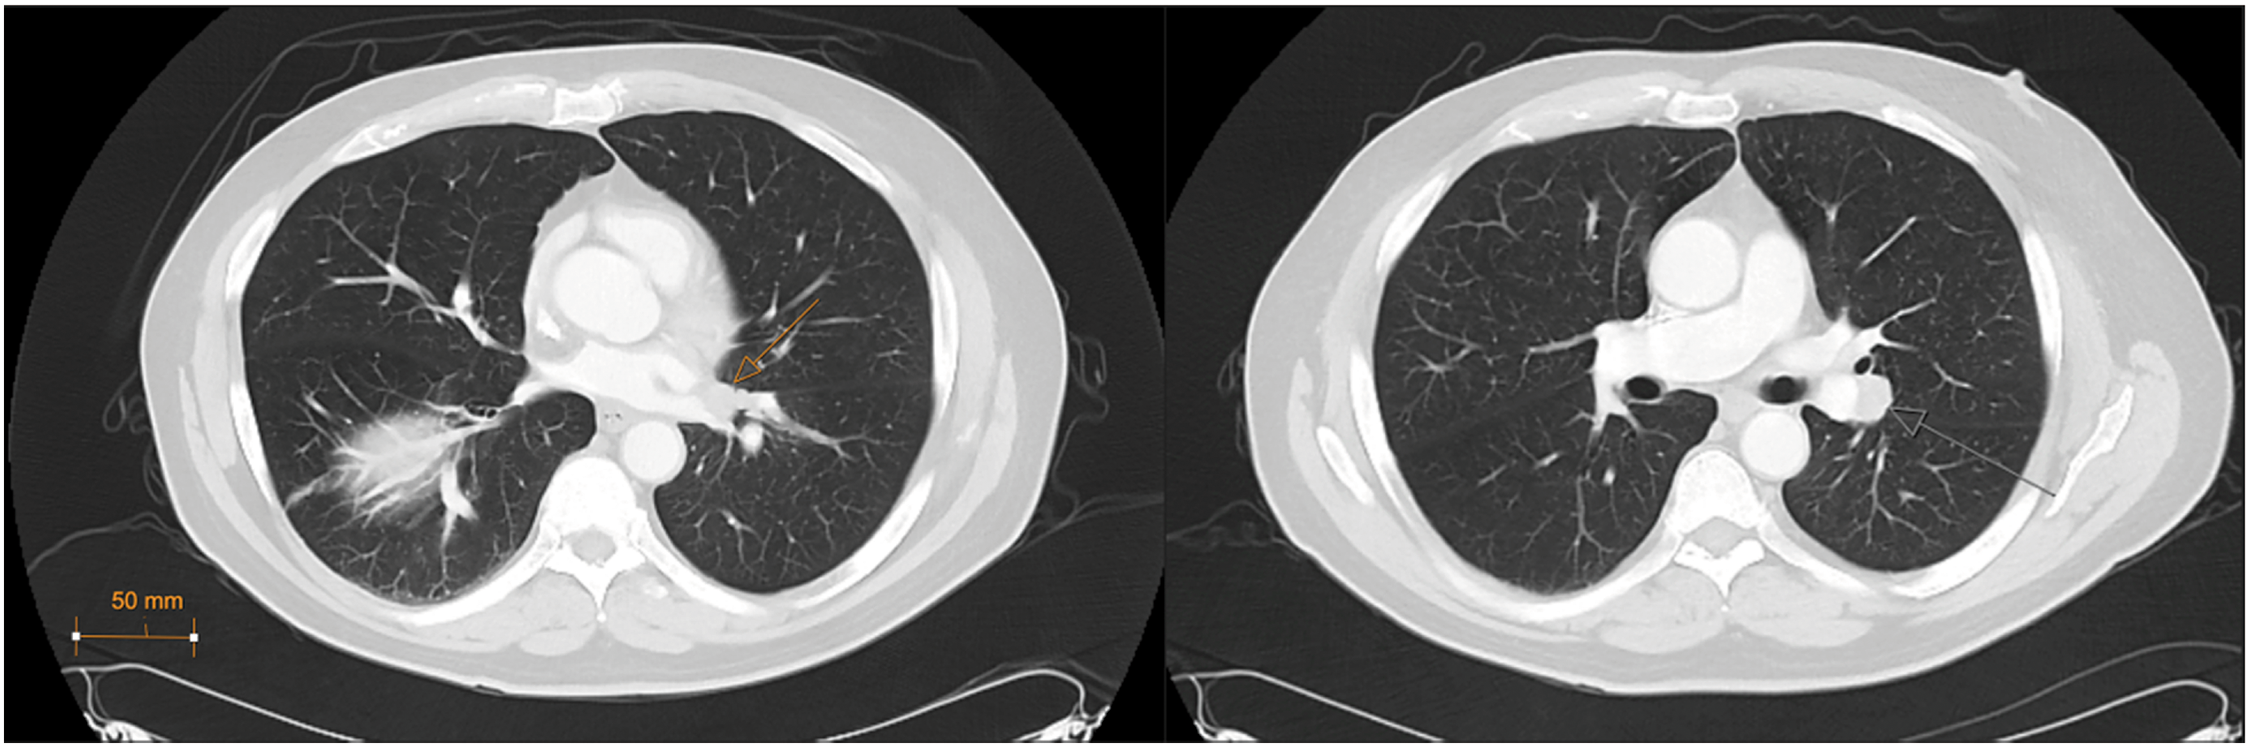

A 69-year-old male presented to the urology clinic with a renal mass incidentally found on CT after presentation to the emergency department with cholecystitis. Cross-sectional imaging identified an enhancing 3.3 × 2.6 cm exophytic mass of the lateral right kidney (Figure 1), and notably, lung adenopathy in the left hilum (Figure 2), initially concerning for metastasis from a renal primary. The patient was referred to interventional radiology and biopsy of the renal mass and hilar lymph nodes. The renal mass biopsy was completed successfully, but the hilar adenopathy was unable to be accessed percutaneously. Review of renal lesion pathology demonstrated a component of oncocytoma with a secondary component of low-grade spindle cell NET.

Figure 2: Left hilar lesions, CT Chest (axial, lung window) (7/14/2023)

Due to the unusual pathology, the case was discussed at our institution’s genitourinary tumor board, and consensus was to proceed with bronchoscopy to access the left hilar lesion. A fine needle aspiration of the 1.8 × 1.6 cm lymph node conglomerate surrounding the left hilar vasculature stained positive for synaptophysin and chromogranin A, identifying the mass as a well-differentiated NET. At this point, serum chromogranin A was obtained, which was mildly elevated at 132. A fluorodeoxyglucose (FDG) PET scan was subsequently performed to better evaluate the degree of metastatic disease, which did not demonstrate any additional foci of NET.

After the hilar node pathology and PET scan were reviewed with the genitourinary tumor board, it was determined that the hilar mass was, in fact, the primary tumor and had likely metastasized to the right kidney. He was referred to cardiothoracic surgery to discuss resection of the primary NET, but due to the central location between the upper and lower lobe bronchial bifurcations and concern for infiltration of disease past the interlobar fissure, the cardiothoracic team determined resection may require left pneumonectomy. He was therefore instead offered observation or radiation therapy to primary NET with subsequent right partial nephrectomy, and the patient elected to pursue treatment.